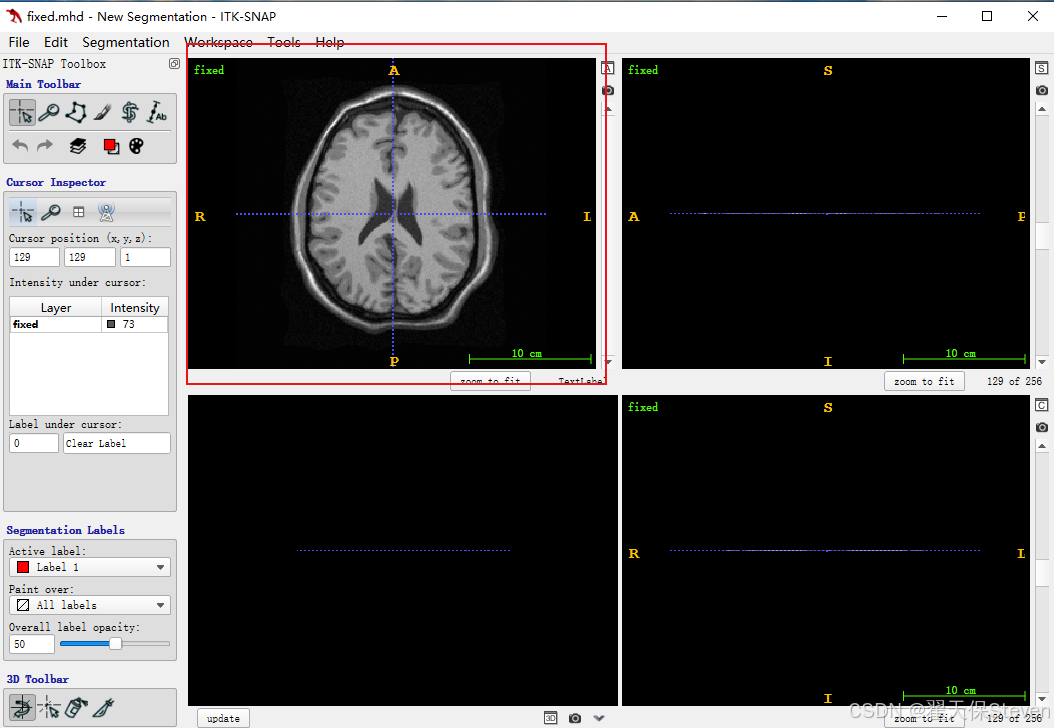

3)加载fixed.mhd成功如下所示。